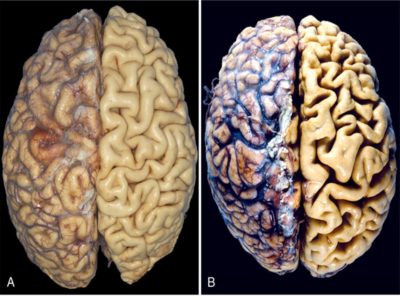

Гипоксия и асфиксия, происходящие в родах и в период новорожденности, не проходят бесследно и могут оказать негативное воздействие на развивающийся мозг. Исходом может стать значительная потеря нейронов, дистрофические изменения нервных клеток в коре головного мозга и в подкорковых структурах и желудочках головного мозга.

Атрофия головного мозга – это процесс омертвения его клеток, а также разрушение соединений, связывающих нейроны. Данная патология может охватывать корковую и подкорковую зоны, приводя к полному разрушению личности человека и делая невозможной его последующую реабилитацию.

Является следствием гипоксии (недостаточного количества кислорода) и дефицита поступающих к нейронам питательных веществ. Это приводит к повышению плотности ядра и цитоплазмы клеток, что влечет за собой уменьшение их объема и вызывает развитие деструктивных процессов.

Структура нейронов может не только атрофироваться, но и полностью разрушаться, а, значит, клетки будут просто исчезать, приводя к уменьшению веса головного мозга в целом.